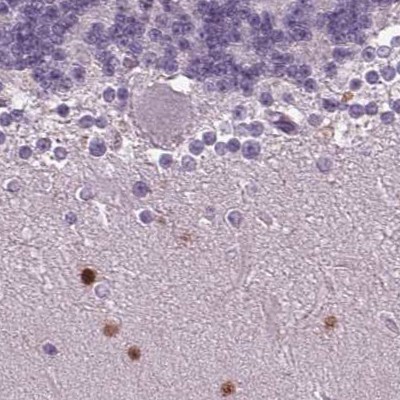

Immunohistochemical staining of human cerebellum, colon, liver and testis using Anti-BHLHE22 antibody HPA064128 (A) shows similar protein distribution across tissues to independent antibody HPA064872 (B).